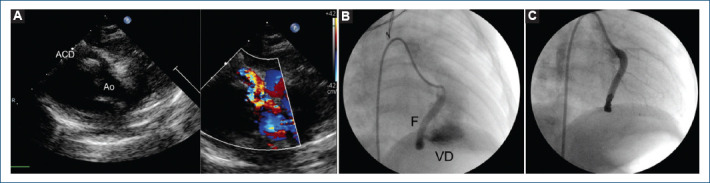

[Endovascular closure of coronary fistula in the infant].

{"title":"[Endovascular closure of coronary fistula in the infant].","authors":"Justo J Santiago-Peña, José F Saaibi-Solano, Andrés F Rubio-Duarte, Iván A Pinto-Martínez, Yudisay Molina-Mora, María I Díaz-Caraballo","doi":"10.24875/ACM.23000216","DOIUrl":null,"url":null,"abstract":"","PeriodicalId":93885,"journal":{"name":"Archivos de cardiologia de Mexico","volume":" ","pages":"515-518"},"PeriodicalIF":0.0000,"publicationDate":"2024-05-08","publicationTypes":"Journal Article","fieldsOfStudy":null,"isOpenAccess":false,"openAccessPdf":"https://www.ncbi.nlm.nih.gov/pmc/articles/PMC12148545/pdf/","citationCount":"0","resultStr":null,"platform":"Semanticscholar","paperid":null,"PeriodicalName":"Archivos de cardiologia de Mexico","FirstCategoryId":"1085","ListUrlMain":"https://doi.org/10.24875/ACM.23000216","RegionNum":0,"RegionCategory":null,"ArticlePicture":[],"TitleCN":null,"AbstractTextCN":null,"PMCID":null,"EPubDate":"","PubModel":"","JCR":"","JCRName":"","Score":null,"Total":0}